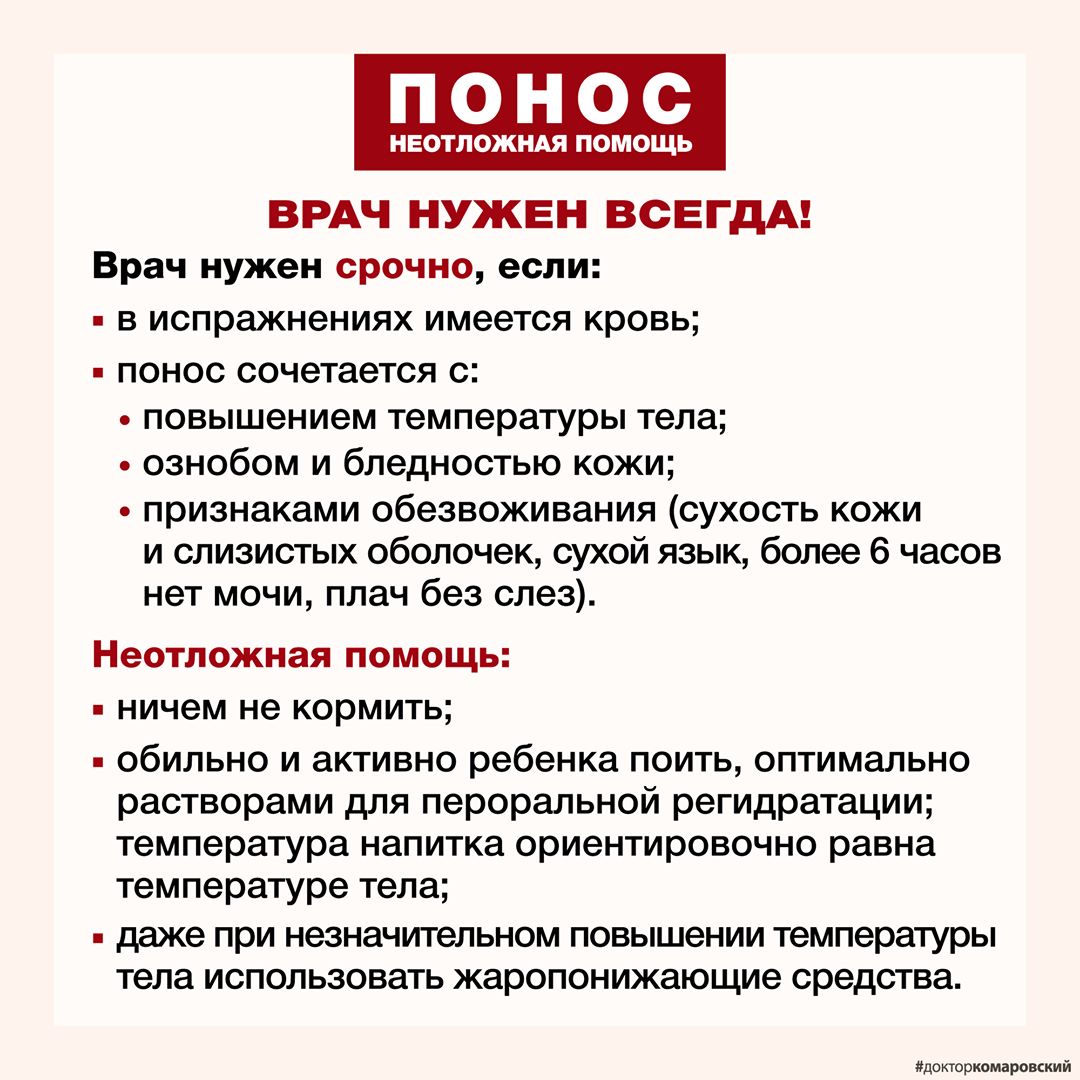

Диарея

Диарея

Диарея

Диарея

У ребёнка понос без температуры